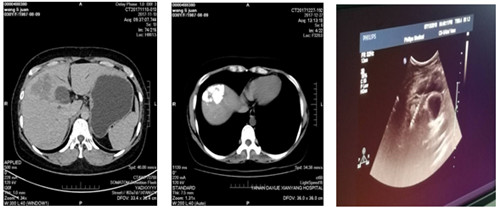

2018年5月前我院腫瘤胸外科收入一年輕女性患者,檢查確診為肝癌,經腫瘤多學科會診后,行多次肝動脈灌注化療栓塞術,治療過程順利,現復查CT示碘油沉積區域面積較前減小。為使病人得到最佳治療,在我院腫瘤病院張海濤院長主持下,召開了腫瘤多學科會診MDT,經過充分的討論,制定了嚴謹的治療方案,確立現在的最佳治療方法為無痛肝癌射頻消融術。

在腫瘤胸外科苗滿園主任帶領下,由腫瘤外科、超聲科及手術麻醉科組成的肝腫瘤微創治療團隊,在鎮痛麻醉后超聲引導下將電極準確插入肝腫瘤內部,采用雙針電極對肝腫瘤進行射頻消融手術。整個手術過程約40分鐘,達到了預期滿意效果及消融范圍。術后患者有輕微不適,無出血及鄰近臟器損傷。